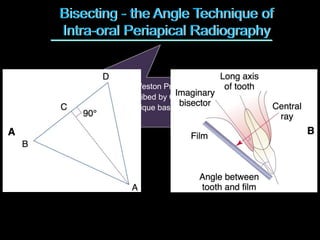

2. The paralleling cone technique provides accurate images with little magnification and no superimposition but is more difficult for patients. The bisecting angle technique is easier for patients but results in more image distortion.